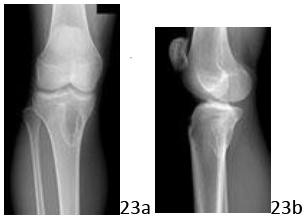

4. # 23a 23b A 15-year-old girl is referred to your office by her primary care physician who is concerned about a "shadow on the bone" noted when office radiographs were obtained following a minor soccer accident. The patient denies any history of knee pain, and has been fully active without any restrictions. Examination is consistent with a minor sprain but otherwise is unremarkable. The lesion is shown in Figures 23a and 23b. What is the most likely diagnosis?

DISCUSSION: The AP and lateral radiographs reveal a lytic, eccentric, well-marginated (mildly sclerotic) lesion that is minimally expansile of the cortex (on the lateral image). This is the classic appearance of a nonossifying fibroma, which most commonly appears

in the metaphyseal region of the lower extremity long bones, particularly around the knee, and in a young patient population. The lesion may also have a "bubbly" appearance, which is not demonstrated in this particular case. Unless the lesion is large, or accompanied by a pathologic fracture, they are generally incidental findings, as in this patient. Giant cell tumor is a more destructive lesion that is typically subchondral in location generally in somewhat older patients. Osteofibrous dysplasia, which may have a somewhat similar appearance, is almost always diaphyseal in location and typically involves the anterior cortex. Enchondroma is not typically eccentric, and while it may have a lytic appearance, usually demonstrates mineral density in the lesion, and is not generally sclerotic at the margin. Infection may have an extremely variable radiographic appearance, but would typically appear more aggressive and present with underlying symptoms. The Preferred Response to Question # 23 is 1.